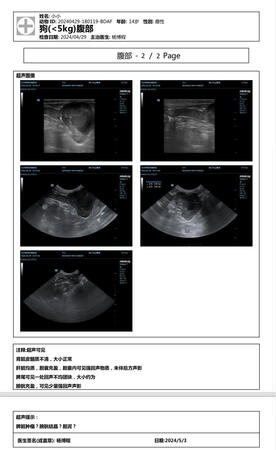

A poodle.

Illnesses